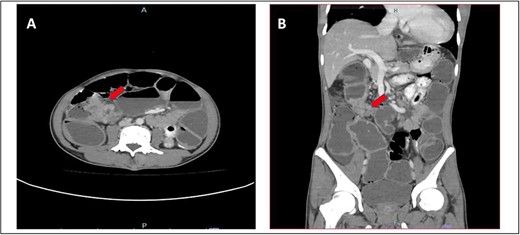

He presented with a history of abdominal distension for 1 week, loose stool, and vomiting for 3 days. Since admission to the ward, he had no bowel opening and did not pass flatus. On examination, he appeared dehydrated, and his abdomen was soft but distended. Plain abdominal radiograph showed dilated bowel. Computed tomography of the abdomen and pelvis showed short segment thickening of proximal transverse colon with dilatation bowel proximally, enlargement of mesenteric nodes, and mild ascites (Fig. 1). We proceeded with exploratory laparotomy, right hemicolectomy, and double barrel stoma. Intraoperatively, a noted tumour at proximal transverse colon size of about 5 × 4 cm with proximal bowel dilatation and distally bowel collapsed. Multiple mesocolic nodes were also present.

(A) Axial view and (B) coronal view of computed tomography showed short segment thickening of proximal transverse colon (red arrow) with dilatation of bowel.